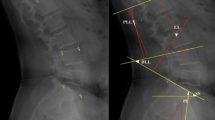

Study participants were equipped with the Epionics SPINE system (Fig. 1) between 7 and 10 a.m. and instructed to perform a series of controlled movements in both the sagittal and transversal planes. The movement sequence began with a relaxed, upright standing posture, followed by maximal upper body flexion, extension, and left and right axial rotations, all performed with knees extended and arms in a relaxed, gravity-directed position. Each movement was repeated six times at the participants’ preferred pace to ensure natural movement patterns. To standardize performance, participants viewed an instructional video prior to the choreography, which demonstrated and explained each exercise.

Data analysis

Data analysis was performed as previously described by Rohlmann et al.16 The thoracolumbar lordosis angle (LA) of the relaxed standing position was defined as a reference value and was determined by calculating the median LA of all six standing postures measured during the short choreography. The LA was defined as the sum of the six most caudal sensor strip segments averaged between left and right strips. Pure flexion and extension of the upper body was characterized by a symmetrical motion in the sagittal plane with almost identical readings at the left and right sensors. Here, the LA at each time frame was determined as the sum of the angles at associated sensor segments. Asymmetric motions of the upper body led to different LAs on the left and right sides of the back. Axial rotation was approximated as the rotation of a line segment connecting the cranial edges of the lordotic segments around the chord of the lordotic arc calculated as an average of the left and right stripes.

For determination of the total number of movements, exactly 24 h (4.32 million frames) of data were analyzed. An eighth-order low-pass Butterworth filter with a cut-off frequency of 5 Hz was used to filter the recorded raw data from the sensor strips and eliminate noise. Movements were counted if they were greater than 5° and were grouped into movement sizes of 5–10°, 10–15°, and > 15°. A movement considered the starting LA and was ended when a countermovement of > 5° was detected. Thus, a movement of -15° could be from a flexed posture of 45° to a less flexed posture of 30°. Based on a certain LA in the sagittal plane and a certain rotation angle in the transverse plane, a movement was counted separately as forward (+) / right rotation (+) and backward (-) / left rotation (-). Lying down was identified based on the accelerometers’ orientation and a reduction of variance in the accelerometer data. The longest period of lying down was defined as sleeping and was omitted from the analysis.